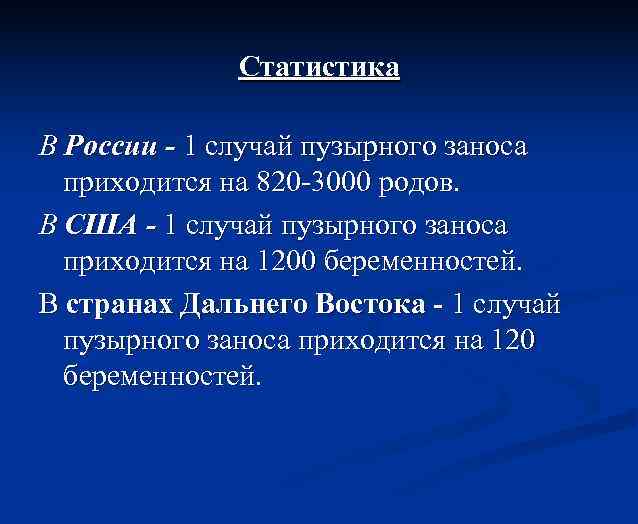

Статистика В России - 1 случай пузырного заноса приходится на 820 -3000 родов. В США - 1 случай пузырного заноса приходится на 1200 беременностей. В странах Дальнего Востока - 1 случай пузырного заноса приходится на 120 беременностей.